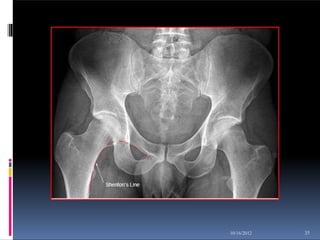

Shenton's

Line

34

10/16/2012

 Shenton's line is a line formed by the

inferior aspect of the superior pubic

ramus and the medial aspect of the

upper femur. Shenton's line should

describe a smooth curve. If there is any

sharp angulation of Shenton's line the

patient could have a neck of femur

fracture. An abnormal Shenton's line

can be the most obvious indicator of a

patient's fractured neck of femur

demonstrated on an AP pelvis /hip

image.